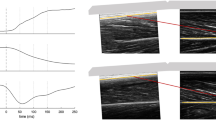

Real-time two-dimensional B-mode US (ECUBE 15, ALPINION Medical Systems, Seoul, Korea) with a 40-mm linear-array transducer (3.0–12 MHz; L3-12T, ALPINION Medical Systems) was used to measure muscle architecture parameters. The muscle thickness and fascicle angle were measured in the anterior thigh and posterior leg region (Fig. 2). The RF, VM, VL, and vastus intermedius (VI) in the anterior thigh region along with the Gm and Gl in the posterior leg region were also measured using US. The anatomical measurement sites are described in detail in Table 4.

Representative US image shown the muscle thickness, fascicle angle, and fascicle length. The muscle thickness was measured between the superficial fascia and the deep fascia (white dashed line) or between the deep fascia and the bone, depending on the region. The fascicle angle (θ) was measured as the angle between the fascicle (yellow dashed line) and its superficial or deep fascia. When the fascicle was too long to measure from the origin to the insertion site, the fascicle length was estimated as muscle thickness/sin(θ). P, posterior; I, inferior; S, skin; Sc, subcutaneous tissue; M, muscle.

The muscle thickness was defined as the distance between the superficial fascia and the deep fascia or between the deep fascia and the bone, depending on the region. The fascicle angle was defined as the angle between the fascicle and deep fascia or the bone, depending on the region. Muscles show different morphologies in the anterior thigh, including the hypertrophic region and the fascicle length of the muscle belly. Therefore, the muscle architectures of the RF, VI, and VL (including the muscle thickness and fascicle angle) were measured at the 30%, 50%, and 70% levels between the greater trochanter and the lateral epicondyle of the femur at the anterior thigh (Fig. 3). The fascicle angle of the VM was not measured because its fascicle was highly curved. The muscle thickness and fascicle angle of the Gm and Gl were measured at proximally 20% and 30% between the fibular head and the lateral malleolus.

The fascicle from the origin to the insertion site was too long to measure using US (Fig. 2), and so its length was calculated as muscle thickness/sin (fascicle angle), where the muscle thickness and fascicle angle were measured using image analysis software (Image J, National Institutes of Health, Bethesda, MD, USA).